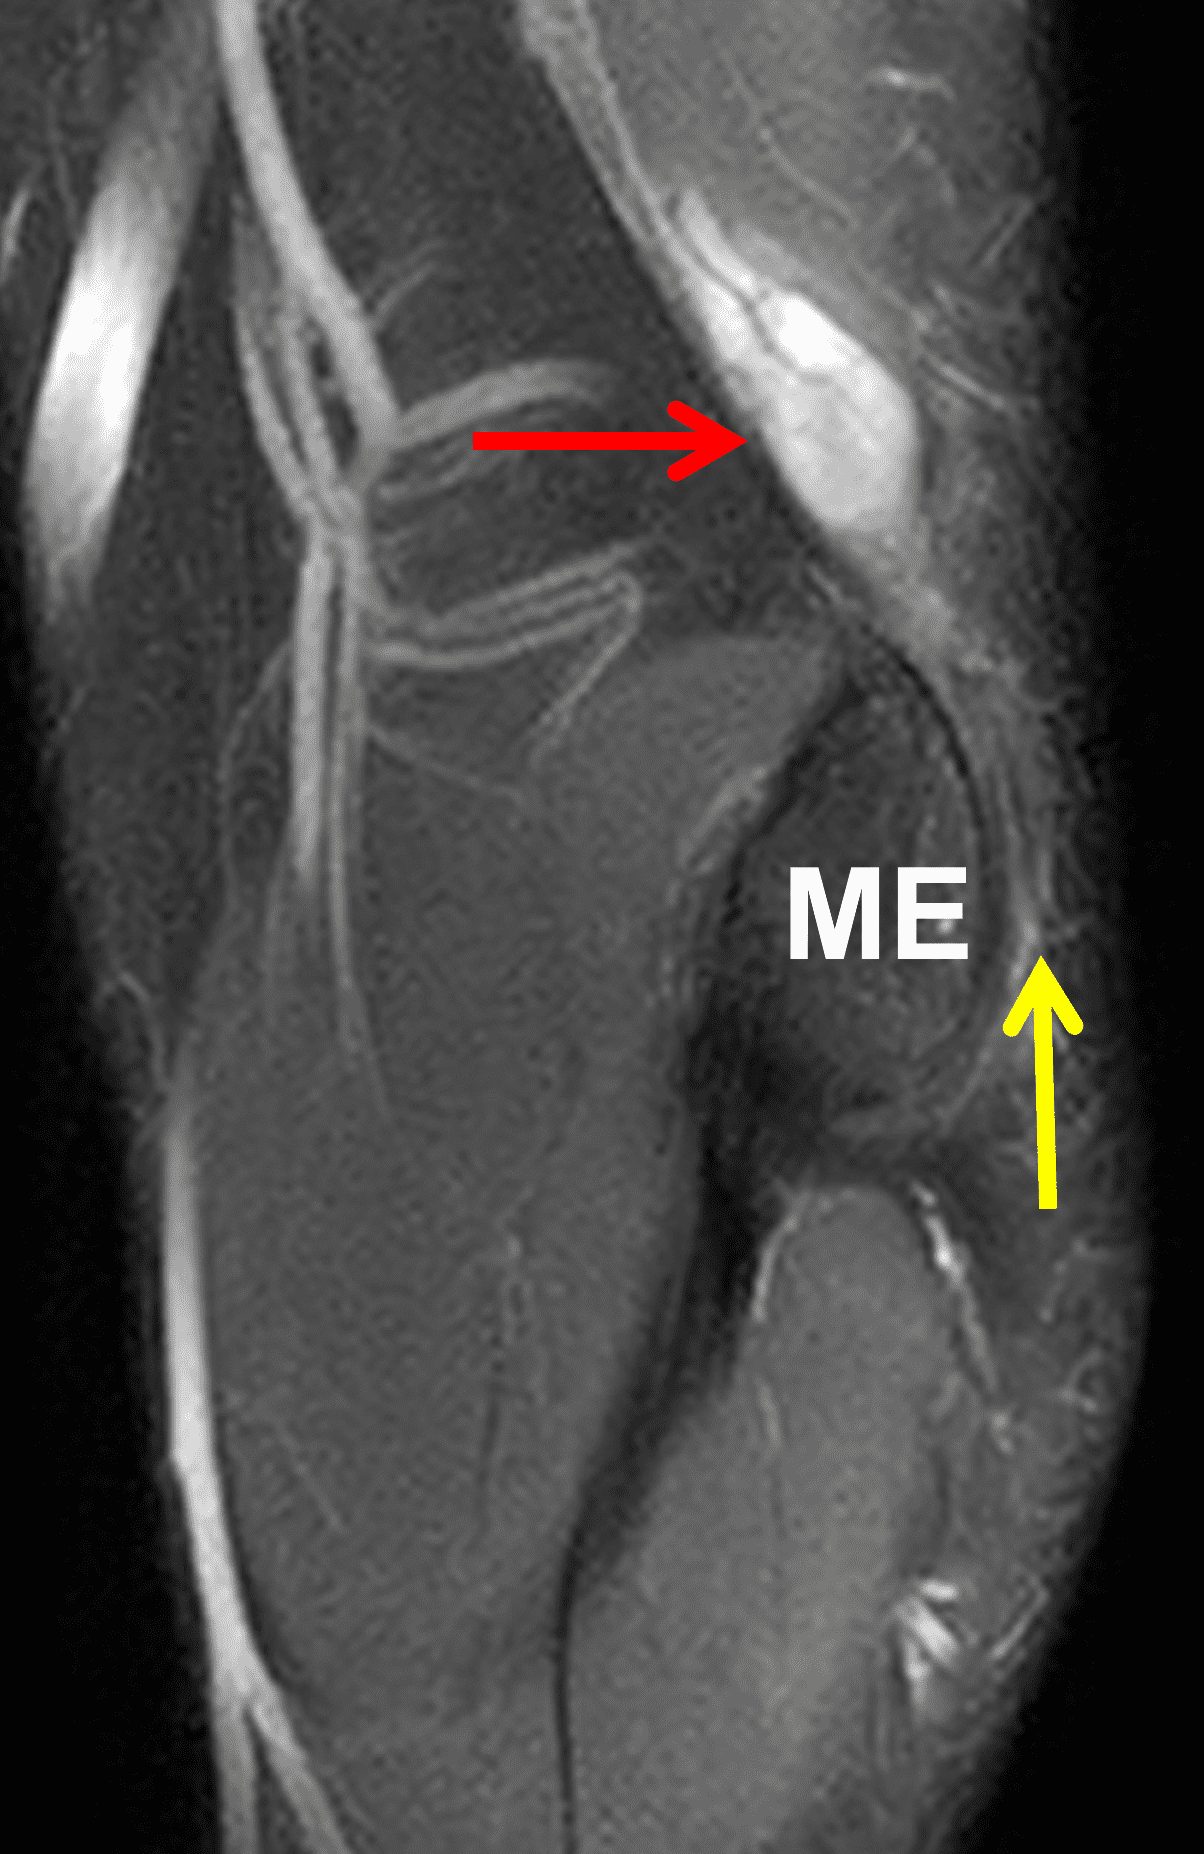

Figure 10: 32-year-old man with a post-traumatic neuroma that developed following an ulnar nerve laceration. Axial (10A) T1-weighted and (10B) fat-suppressed, fluid-sensitive sequences demonstrate enlargement and disorganized architecture of the ulnar nerve (arrows) proximal to the cubital tunnel. (10C) On a sagittal fat-suppressed, fluid-sensitive image, no nerve fibers are visible posterior to the medial epicondyle (ME) in the cubital tunnel (yellow arrow), the site of the nerve transection. The post-traumatic neuroma (red arrow) involves the proximal nerve stump. (10D) An axial fat-suppressed, fluid-sensitive image in the proximal forearm shows subacute denervation with the flexor digitorum profundus muscle (asterisk).